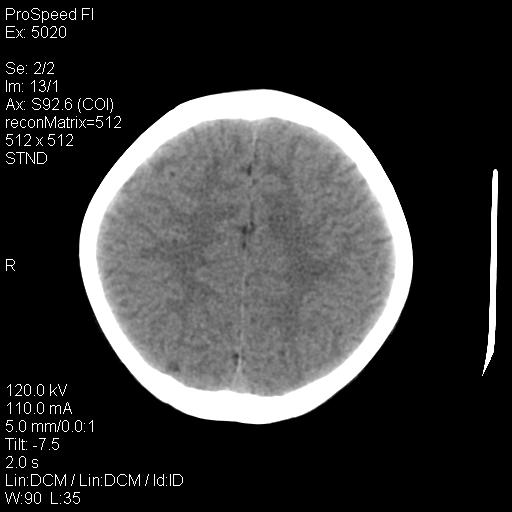

标题: PED1637:M 6Y 顶部无痛性包块两月。 [打印本页]

标题: PED1637:M 6Y 顶部无痛性包块两月。

2、颅骨局部缺失,边缘光滑、整齐

颅骨的病损表现为内外颅骨板层不规则的锋利的破坏,形成“斜边缘”,有一定的特点

颅骨为好发部位,生长缓慢,常位于顶骨、枕骨及颞骨,表现为颅骨缺损,呈圆形或椭圆形,边界清,无硬化

事发冠状缝与矢状缝交界区,密度较低,考虑表皮样囊肿可能性大,其次不除外嗜酸性肉芽肿